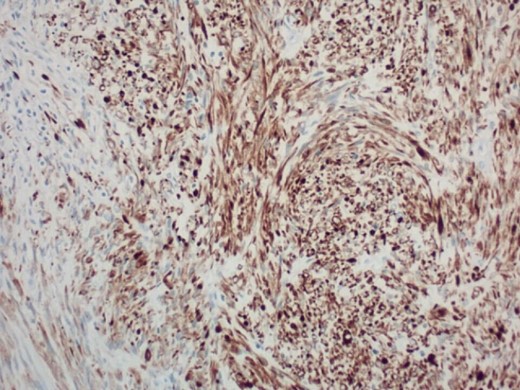

Pathology report was significant for mitotic figures on hematoxylin and eosin stain (Fig. 4). Immunohistochemistry showed actin positivity (Fig. 5) and desmin positivity (Fig. 6) in the tumor cells. All lymph nodes and margins were negative, with the smallest margin measuring 1.5 cm. The findings listed in the pathology report were consistent with primary leiomyosarcoma of the small bowel.

200× magnification of tumor cells. Immunohistochemical stain for desmin is positive.